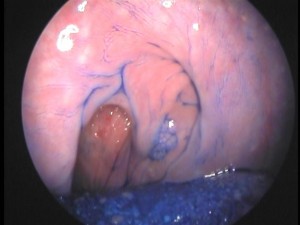

Con cromoendoscopía se visualiza superficie mucosa infectada por HPV en la hemilaringe izquierda. Los papilomas se observan como pequeñas verrugas, cada una con su eje vascular.

Magnificacion de la superficie mucosa infectada por HPV. Puede observarse el eje conectivo vascular a partir del cual se desarrollan las verrugas